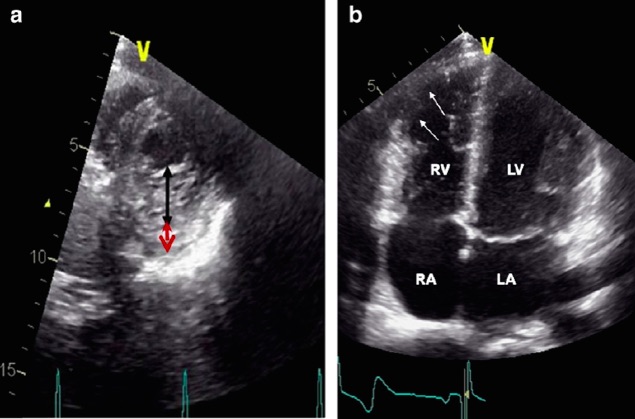

Las siguientes imágenes ecocardiográficas corresponden a dos triatletas no profesionales que participaron en el Ironman de Zúrich en 2010.

Ambas imágenes cumplen criterios ecocardiográficos diagnósticos de enfermedad cardíaca con riesgo de muerte súbita (a: miocardiopatía no compactada; b: displasia arritmogénica del ventrículo derecho).… pero la realidad del caso es que se trata de dos casos de corazón de atleta.

Así se demostró mediante novedosas técnicas de ecocardiografía (TDI: Tissue Doppler Imaging y STI: Speckle Tracking Imaging), capaces de medir la funcionalidad de la fibra muscular cardíaca (miocárdica), alterada en enfermedad cardíaca y normal o en muchos casos mejorada en corazón de atleta.